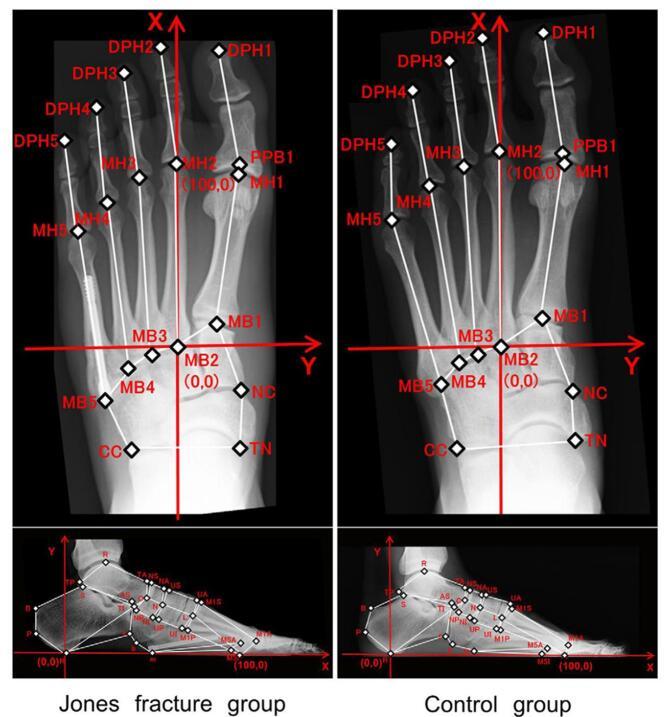

Our systematic review analyzed 26 studies with 8514 participants. Young age was a risk factor in four studies, and female gender in one. High body mass index, increased training hours, competitions, and intense preseason training also raised risk. Anatomical factors included lower calcaneal pitch angle, wider medial malleolar slip angle, higher Talocalcaneal angle, and lower limb varus malalignment. Stress fractures were higher among midfielders in one study, while two others found no positional differences. Additional risks were elevated parathyroid hormone, higher bone-specific alkaline phosphatase, lower 25OH levels, fasting, and perceived stress from negative life events.

我们的系统评价分析了26项研究,涉及8514名参与者。四项研究表明年龄小是一个风险因素,一项研究表明女性是风险因素。高体重指数、训练时间增加、比赛次数和季前强化训练也会增加风险。解剖学因素包括跟骨倾斜角较低、内踝滑动角较宽、距跟角较高以及下肢内翻畸形。一项研究表明中场球员应力性骨折发生率较高,而另外两项研究未发现位置差异。其他风险因素包括甲状旁腺激素升高、骨特异性碱性磷酸酶水平较高、25OH水平较低、禁食以及负面生活事件带来的感知压力。